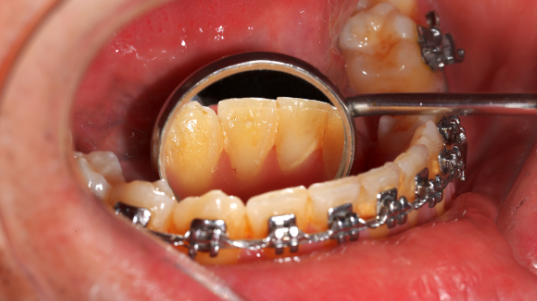

··托槽矯治器

呢個主要係因為矯治器需要黏喺牙齒上,同埋裝有弓絲,會形成一些清潔死角,令病人刷牙多咗啲不便。所以,當矯正牙齒時病人需要認真使用各種刷牙工具同埋延長刷牙時間,減少清潔死角,保持良好嘅口腔衛生狀態,降低易齒齲機會。

唔然牙面會有食物殘渣,會漸漸形成細菌結石、令牙齒脫礦同埋齒齲。